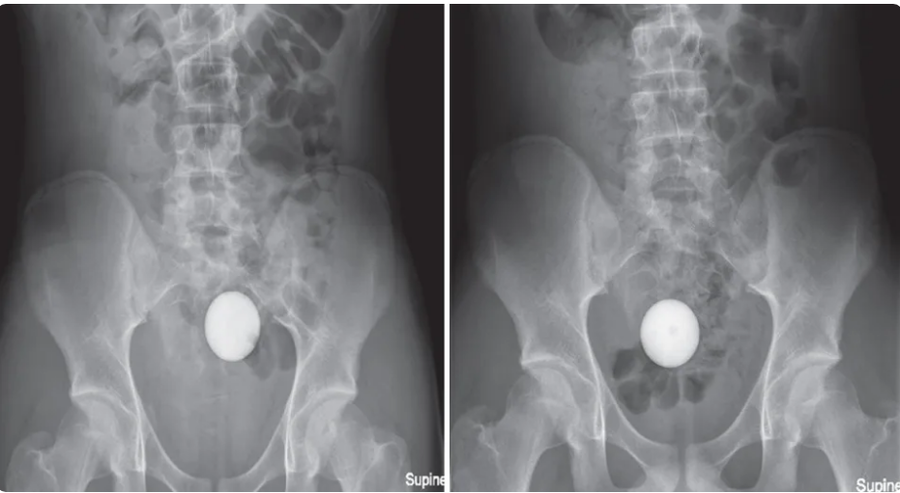

The teenager was not in pain, and the ball was not affecting his bowel movements. An X-ray showed the golf ball was lodged in the boy’s sigmoid colon, making removal challenging for the doctors. An intensive procedure to physically extract the ball went on for two hours under general anesthesia. Despite trying various methods, such as a suction cup, medical net, quad-prong grasper, and balloon catheter, the doctors were unable to achieve success.